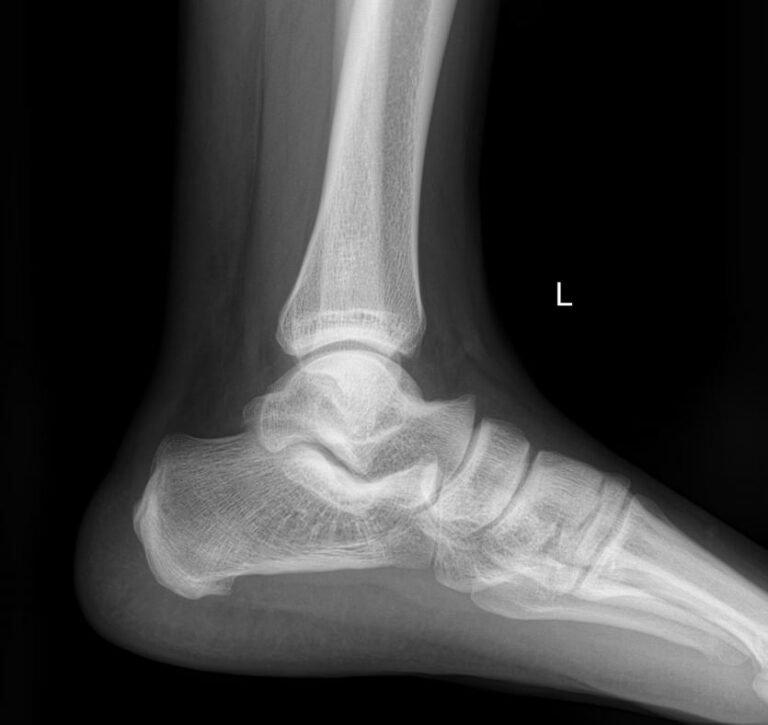

Голеностопные суставы отличаются сложным строением, в позволяющим стопе вращаться, сгибаться и разгибаться почти на 90о. Благодаря этому тело свободно перемещается в пространстве, меняет свое положение, поднимает собственный вес и дополнительный груз. Травмы голеностопных суставов встречаются также часто, как и хронические заболевания.

В качестве скринингового, а зачастую и единственного метода диагностики голеностопных суставов обычно используют рентген. Его вполне достаточно для визуализации внутреннего строения сустава и патологических изменений в нем. А цифровая нагрузка цифрового оборудования последнего поколения  несет минимум излучения и позволяет безопасно делать несколько снимков подряд.

Что покажет рентген голеностопных суставов

• Изменения, произошедшие в костной ткани элементов суставов ― разрежение, некроз, озлокачествление, склерозирование;

• Нарушение четкости контуров костных образований;

• Перелом, его местоположение, смещение отломков;

• Состояние суставных щелей ― сужение, расширение, скопление жидкости, обызвествление капсулы;

• Конгруэнтность суставных поверхностей или вывих;

• Состояние мягких тканей ― отеки, инородные тела.